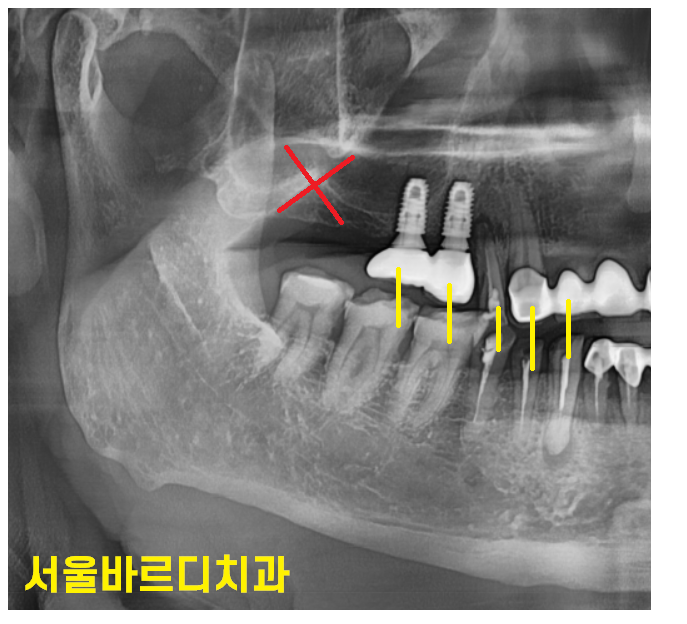

이러한 치아 올라옴과 치아 내려감의 문제가 무엇이냐

음식물이 낄 수 있다는 단점이 생깁니다.

끼는 것 자체로도 굉장히 불편하지만..

240329

끼고 나서 음식물 제거가 잘 안되면

붙어있는 옆에 치아가 썩게 됩니다.

충치가 생긴다는 말이죠~

치아를 뽑고 방치하면 위아래로 옆으로 움직인다.

턱 뼈에 고정되어 있는 것처럼 보여도

치주 인대에 의하여 움직인다.

특히나 잇몸이 안좋으신 분들은

움직임이 빠르기 때문에 빠른 시간안에 치료를 해주셔야합니다.